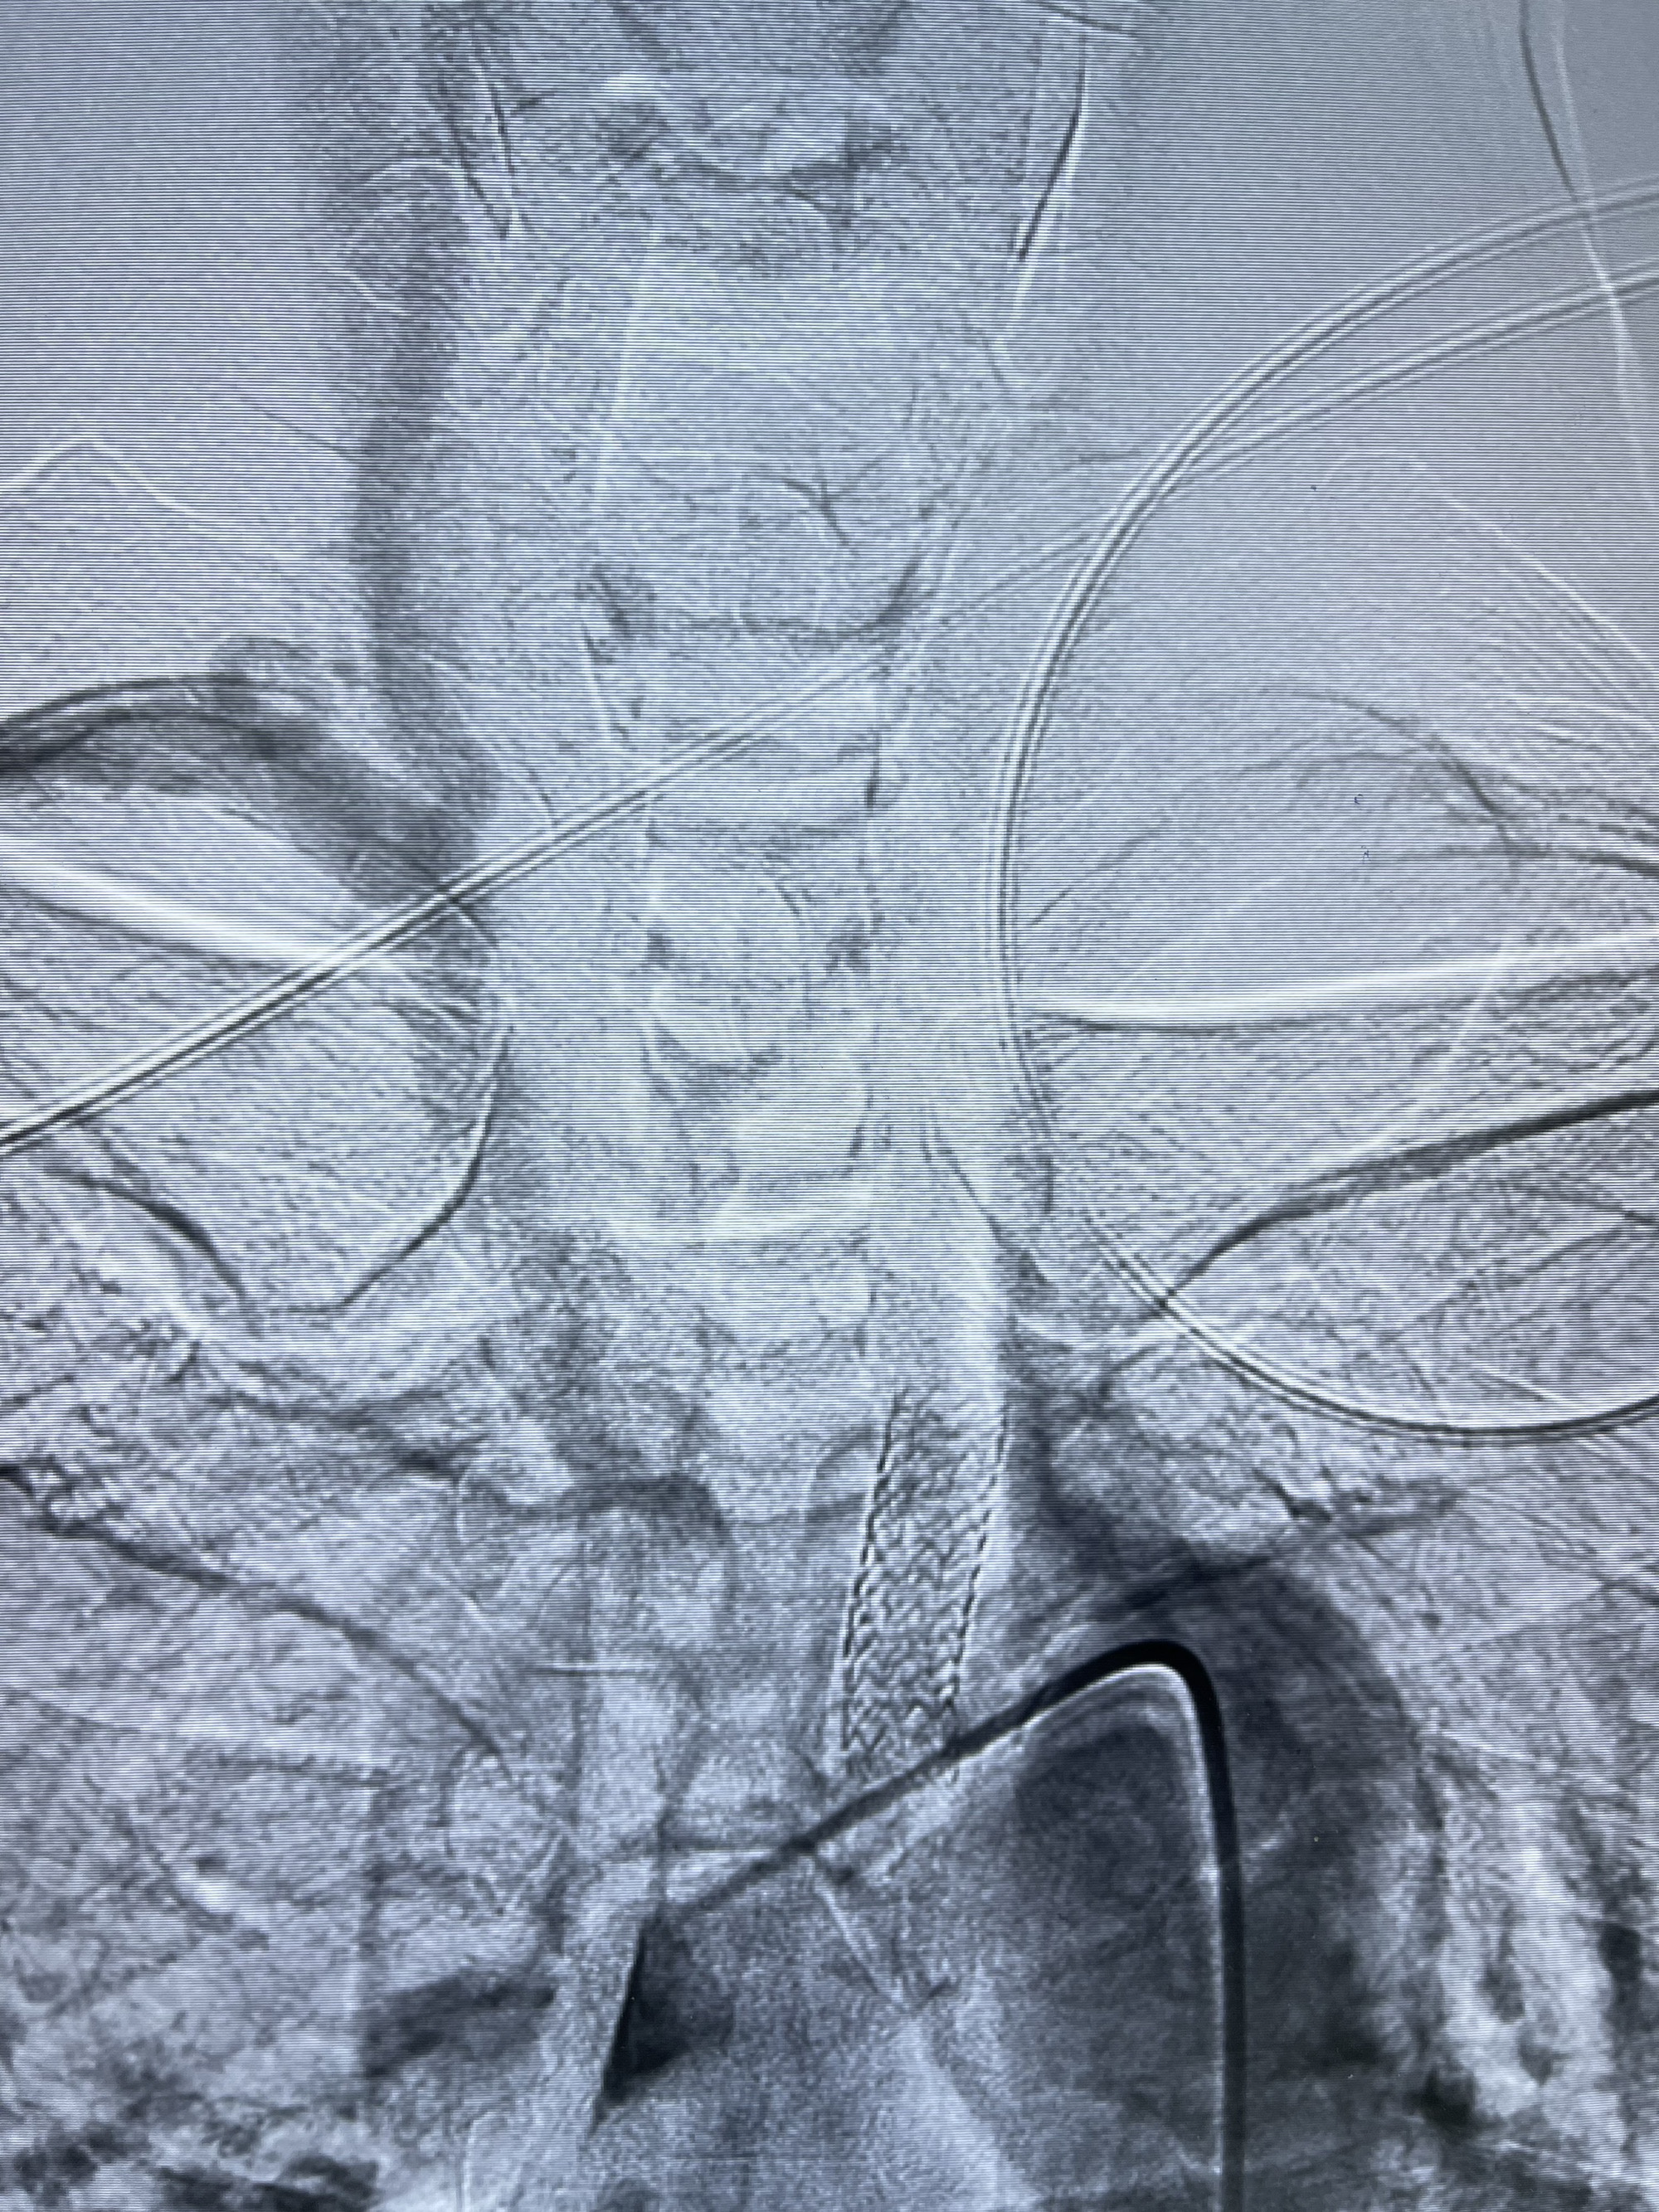

脑血管造影2023.03.06:右侧颈内动脉颈段至岩骨段闭塞,可见后后循环通过原始三叉动脉吻合代偿至海绵窦段,后交通区可见囊状造影剂填充影,左侧锁骨下动脉呈“残端”改变,呈“右侧颈总动脉支架成形术后改变”,支架内血流通畅,可见后交通吻合显影至左侧大脑后动脉,并可见左枕动脉吻合椎动脉至锁骨下动脉

2023-03-06DSA:

1.右侧颈内动脉及左侧锁骨下动脉闭塞

2.右侧颈内动脉由后循环经右侧后交通动脉前向代偿显示

3.右侧颈内动脉眼动脉段近后交通动脉处重度狭窄伴前壁不规则动脉瘤

4.右侧颈外动脉可见经由右侧脑膜中动脉吻合显影右侧眼动脉及颈内动脉

1.箭头处为右侧颈内动脉后交通动脉处重度狭窄,狭窄前壁为不规则动脉瘤;

2.狭窄远端颈内动脉由左侧颈内动脉经左侧后交通动脉—基底动脉顶—右侧后交通—右侧颈内动脉—右侧大脑中动脉途径代偿

左侧颈内动脉经左侧后交通动脉—基底动脉顶—右侧后交通—右侧颈内动脉—右侧大脑中动脉途径代偿